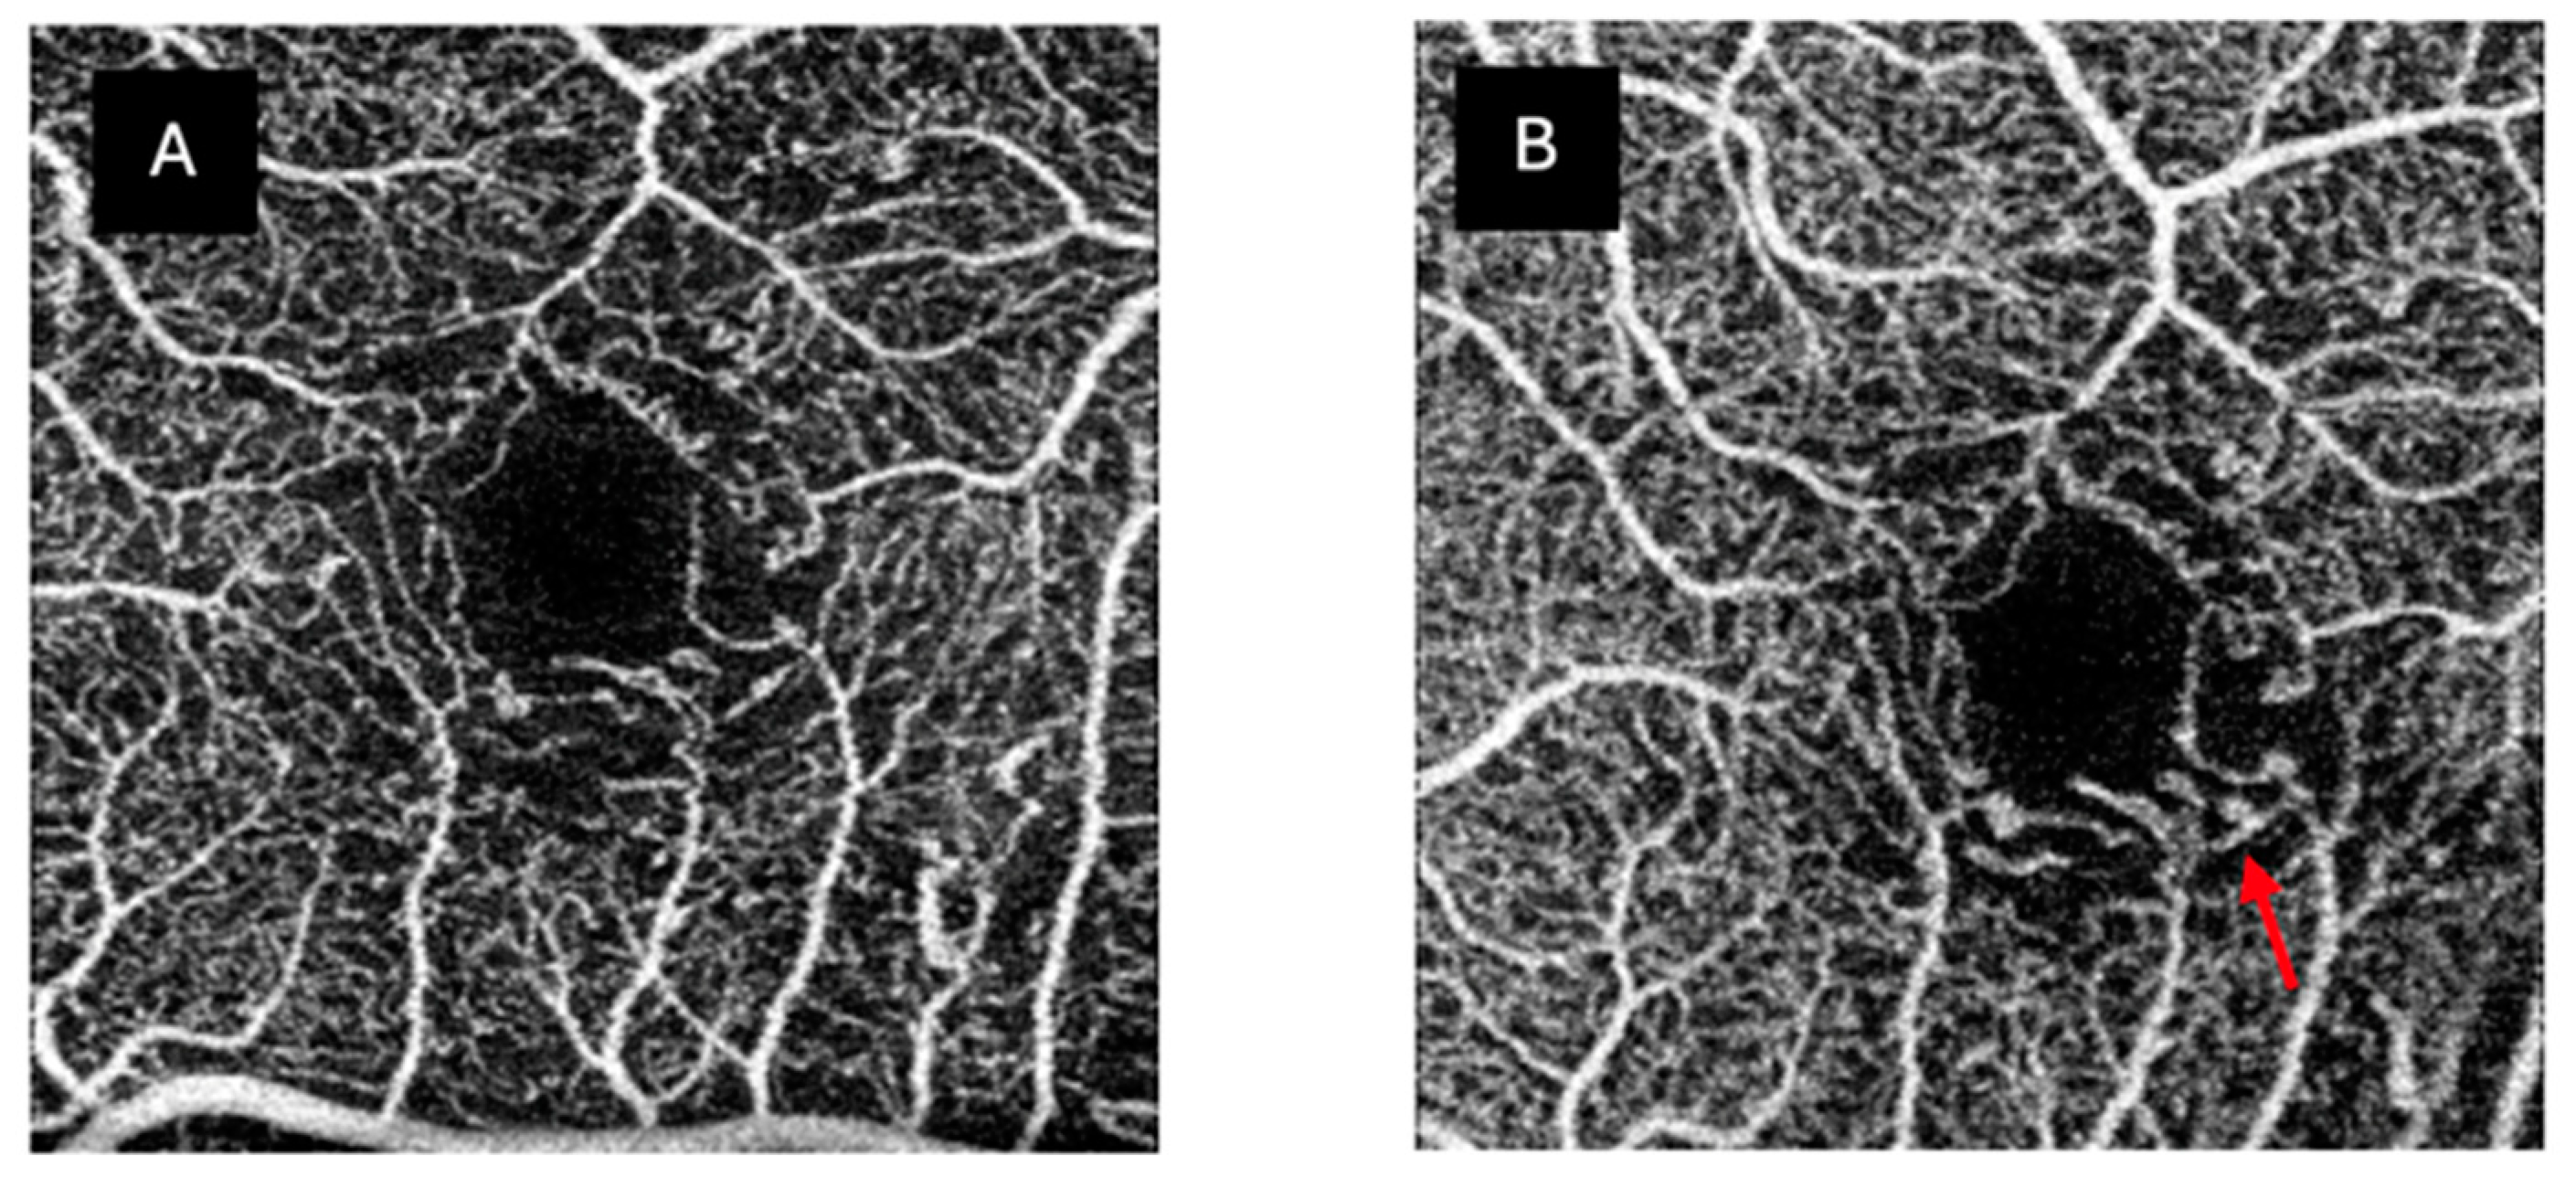

| FAZ abnormalities | 92% | 88% | |

| Marked ischaemia | 4% | 4% | 0% |

| Capillary dropout | 96% | 96% | 76% |

| MA | 8% | 20% | |

| Normal | 4% | 4% | 24% |